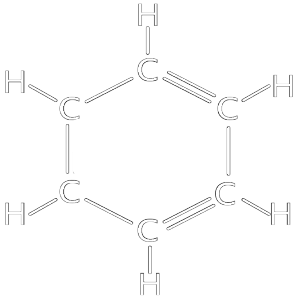

BENZENE